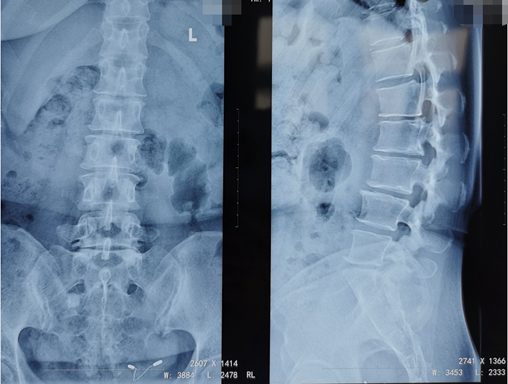

熊东主任接诊后,结合赵女士的查体及其他各项检查结果,确诊她为“腰椎间盘突出症(腰5骶1)”。赵女士在腰5骶1处已经出现比较严重的突出且已压迫到神经,而且症状严重影响生活,建议进行椎间孔镜手术微创治疗。

术前影像学资料